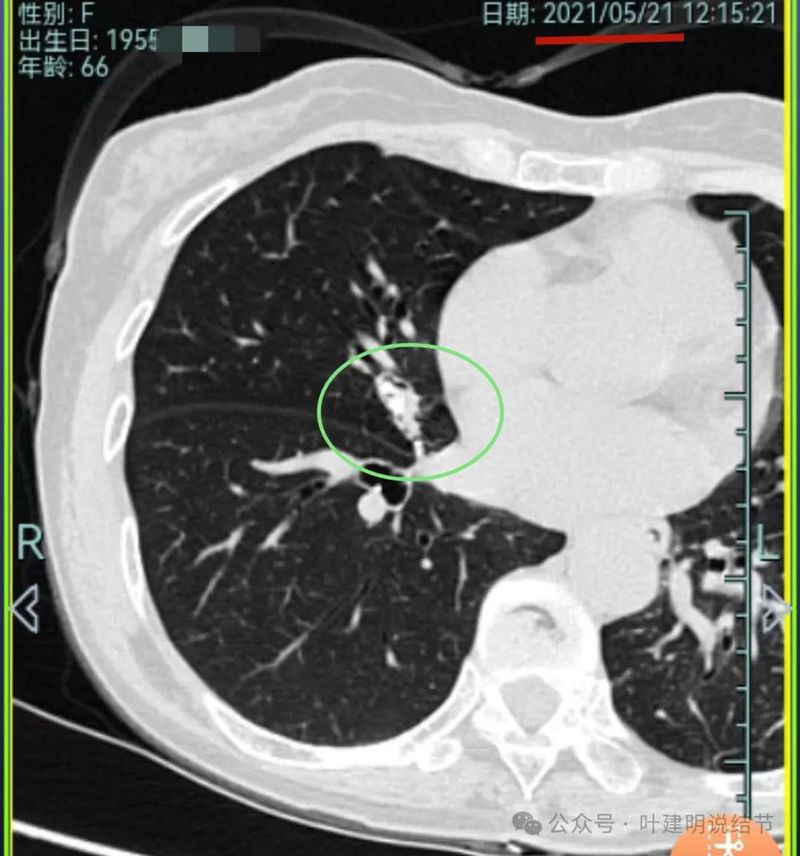

再看2021年随访的影像:

病灶3仍是混合密度,进展不显著。

我想我们这样也来考虑问题:1、左侧已经手术的确诊是肿瘤性质,左上已经消融的也是随访持续存在的磨玻璃密度结节,虽然没有病理依据,仍然要考虑广义上来讲的肿瘤范畴,看了以前的片子,从2019年到2023年并没有显著的进展,大概是肺泡上皮不典型增生可能性大。右侧的也有磨玻璃结节与混合磨玻璃结节考虑是肿瘤范畴的。所以总体上两肺多原发早期以磨玻璃为表现的肺癌,整体风险都不大。2019年切除的左肺下叶病灶也是纯磨玻璃密度,其实如果继续随访或者只做楔形切除也并没有什么关系。这说明体质本身或者致病的因素,就是容易长磨玻璃肺癌的,即便把目前发现的都解决,后续仍可能再有新的。原因不明,致病因素仍在。2、右肺上叶红色之处从2019年开始,是逐渐进展的,当然即便是现在,也不是说危险就已经很大,考虑仍然是原位癌或者微浸润性腺癌可能性大;中叶蓝色这处乍一看像至少是微浸润,但前后对比以后发现从2019年到现在,几乎没有显著进展,这样的话慢性炎伴肺泡上皮增生或者伴纤维增生也是有可能的,至少风险并不能认为大;右肺下叶黄色这一处,使纯磨玻璃密度,整体轮廓与边界清楚,考虑是肿瘤范畴的,不典型增生可能性较大,也有可能原位癌,随访稍有进展,风险仍然不大;中叶绿色这处是慢性炎伴钙化的,靠近叶裂的地方也像慢性炎,但此处随访有所进展。不过因为有卫星灶,整体显得比较散,所以虽然恶性可能性较大,但也不能完全除外炎性的可能性。当然如果此灶确实恶性,那风险则相对较其他进展缓慢的要高一些。从目前右侧所在的这些病灶来讲,真正有一定的风险而且最为确切的是红色这处,而且应该也没有到浸润性腺癌或者说不处理会要转移很危险这种程度。3、明确了多原发早期肺癌没有办法预防与控制,也明白了目前已经存在的较明显的这些病灶总体风险的高低。我们再来考虑需不需要近期干预处理。左侧既手术过又消融过,右侧的多发病灶目前又还没有到危险很高的程度,又没有办法预防后续再有新的病灶。我个人偏保守,我觉得仍然可以半年复查随访,如果最具风险的病灶有进展并且不处理可能导致不良后果,到这样的程度再来考虑综合如何处理干预便可。4、假如右侧我们予以处理,上叶红色的以及中叶蓝色的都可以楔切,但绿色考虑良性的再进展或以后像恶性时怎么办?而若中叶切除加上叶楔切,在左侧已经手术过的情况下肺功能影响相对也不小,何况右下比较中间的位置还有桔色这处呢。当然右下这处得考虑消融。所以,我的想法还是能熬再熬下,待其他监测有变化再通盘考虑。意见供参考!